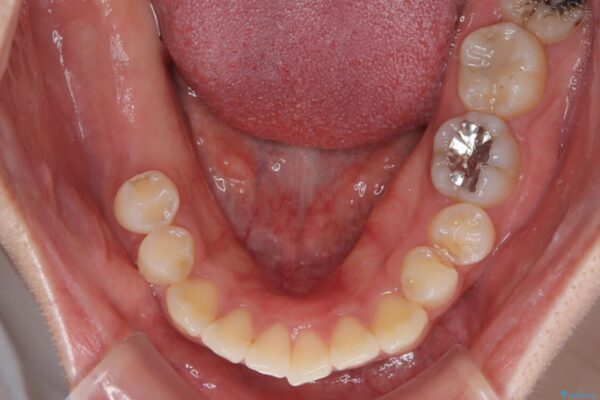

インプラント希望部位は右下第一大臼歯と第二大臼歯です。

しかし、噛み合わせの相手である右上の第二大臼歯が、長期間噛み合う歯がなかった影響で**挺出(歯が下に伸びてくる状態)してしまっており、このままではインプラントを埋入して被せもの(上部構造)を入れるためのスペースが不足している状態でした。

• 挺出歯を圧下してスペースを確保!目立たない部分矯正で下顎大臼歯にインプラント治療を実現 治療前画像